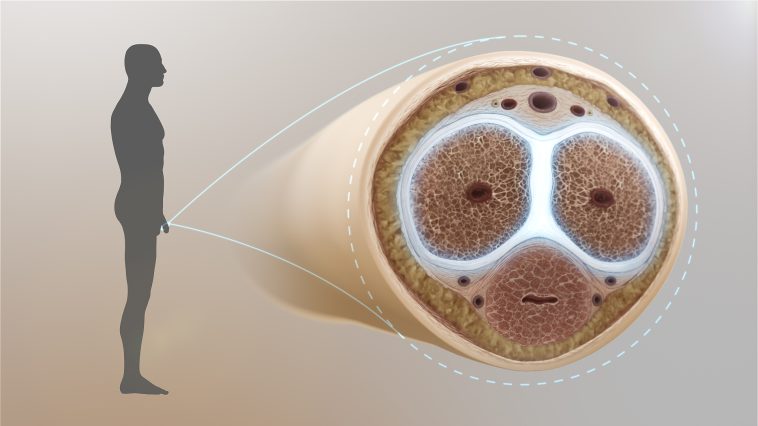

Όπως ανέφερε, κατά τη διάρκεια της πράξης, “κάτι δεν πήγε καλά” και το πέος του έδειχνε να έχει υποστεί ρήξη.

- Οι γιατροί του νοσοκομείου πραγματοποίησαν λεπτή χειρουργική επέμβαση για να αποκαταστήσουν τη ζημιά. Παρόλο που η επέμβαση φαίνεται να ήταν επιτυχής, ο ασθενής αντιμετώπισε σημαντική ψυχολογική δυσφορία από το συμβάν, με πιθανή ανάγκη για ψυχολογική υποστήριξη.